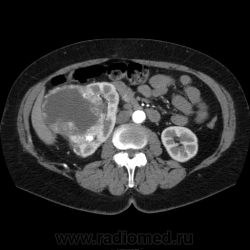

Солитарное кистовидное образование правой почки с неравномерно утолщенными стенками, у узлами в капсуле, накапливающими контраст. Фасция Гарота справа тяжистая. По классификации - киста 4-й категории, крайне велика возможность малигнезации. Может, показалось вовлечение парааортальных лимфоузлов?

В 1986 г. M.A. Bosniak создал “рабочую” классификацию кистовидных образований почек, которая позволяет предположить доброкачественность или злокачественность кистозных образований при распределении их по радиологическим критериям на 4 основные категории. Образования I и II категорий являются заведомо доброкачественными и поэтому нуждаются в динамическом наблюдении или, по показаниям, в лечебной пункции со склеротерапией под контролем УЗИ или КТ. Образования III категории могут быть как доброкачественными, так и злокачественными, а образования IV категории – кистозные почечноклеточные раки.

IV категория – поражения явно злокачественные, обычно кистозные почечно-клеточные карциномы. Основными симптомами кистозной опухоли при КТ являются: неправильная форма кисты, негомогенность структуры образования с участками некроза, деформация почки, нечеткая граница между кистой и паренхимой почки, плотностные показатели могут быть выше, чем в кистах (+20…+40 Н), т.е. близкие к плотности почечной паренхимы. Капсула имеет неравномерную толщину, часто обызвествлена по периферии. Возможна визуализация дополнительных фокусов образования (кажущееся увеличение образования в размерах и изменение его конфигурации) после введения контрастного вещества. Но самым важным симптомом является увеличение плотности внутреннего содержимого после внутривенного введения контрастного вещества. Часто на серии срезов удается выявить эндофитные гребневидные фестончатые разрастания, выступающие в просвет кистозной полости. Особенно хорошо этот мягкотканый васкуляризированный компонент опухоли проявляется при внутривенном контрастировании

Всё верно, я тоже пользуюсь данной классификацией по Босняку, кистозно-солидное образование правой почки я отнёс к 4 категории, нужно отметить, что преобладает кистозный компонент, но солидный компонент довольно приличный и значительно накапливает контрастное вещество до 80-90HU, четко капсулу образования не отграничить. Ко всему этому в паренхиматозную фазу четко дифференцируются единичные парааортальные и паракавалльные л/узлы. С большей степенью вероятности в данном случае cr почки. Пациентка на следующей неделе будет госпитализирована для верификации.

Описание изменений, выявленных при микроскопическом исследовании: опухоль представлена крупными альвеолярными структурами из светлых, оптически пустых клеток с мелкими гиперхромными ядрами, опухоль частично инфильтрирует капсулу почки, полностью прорастает стенку почечной лоханки, образуя полиповидные структуры. Одиночные опухолевые эмболы в сосудах почки. Отдельно присланный узел представлен тканью почки с опухолевым узлом, строение которого соответствует выше описанной опухоли. В воротах почки патологических образований не найдено. Во всех исследованных лимфоузлах (6 шт.) метастазы опухоли с замещением всей ткани лимфоузлов.

Патоморфологическое заключение: массивный светлоклеточный почечно-клеточный рак почки с частичной инфильтрацией капсулы, прорастанием в ЧЛС, опухолевыми эмболами в сосудах, множественными метастазами в забрюшинные лимфоузлы (6 шт